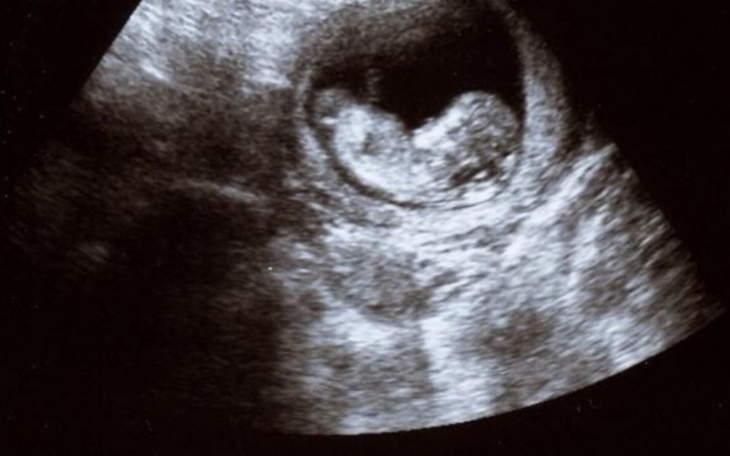

Bardzo proszę o pomoc w zebraniu pieniędzy na pokrycie kosztów leczenia niepłodności. In Vitro niestety przestało być finansowane przez państwo, a wielu ludzi na to nie stać. Bardzo chcemy być z mężem rodzicami i bardzo prosimy o każdą złotòwkę. Jak dotąd pokrywaliśmy koszty leczenia i diagnostyki sami, niestety koszt samego zabiegu in vitro nas przerósł. Mamy mało czasu i sami nie zdążymy uzbierać takich pieniędzy bez Waszej pomocy. Będziemy wdzięczni za każdą złotòwkę. Tak bardzo chcemy usłyszeć bicie serca naszego dziecka!